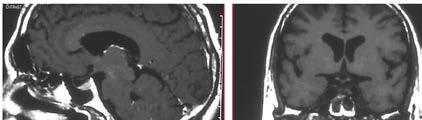

64 Pituitary Gland Tumors (Pituitary Adenomas)

Al Ahli Hospital / Qatar